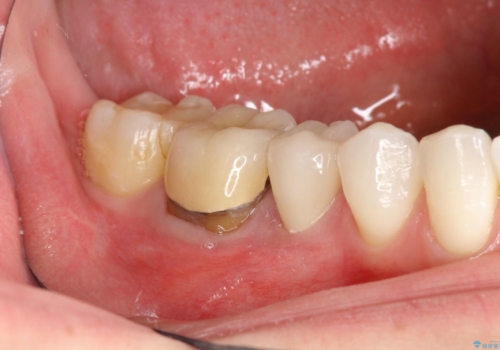

歯肉にできものがある、根管治療からセラミッククラウンまで

右下5,6間にフィステル(瘻孔)を認めました。デンタルより、右下5根尖に透過像を認め、フィステルに材料を入れてレントゲンにて確認したところ、右下5の根尖に到達しました。

右下5の神経は失活してしまっているため、根管治療の必要性を説明の上、根管治療をした後セラミッククラウンを入れていくこととなりました。